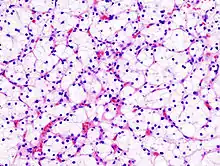

Micrograph of the most common type of renal cell carcinoma (clear cell)—on right of the image; non-tumour kidney is on the left of the image. Nephrectomy specimen. H&E stain

The gross and microscopic appearance of renal cell carcinomas is highly variable. The renal cell carcinoma may present reddened areas where blood vessels have bled, and cysts containing watery fluids.[58] The body of the tumour shows large blood vessels that have walls composed of cancerous cells. Gross examination often shows a yellowish, multilobulated tumor in the renal cortex, which frequently contains zones of necrosis, haemorrhage and scarring. In a microscopic context, there are four major histologic subtypes of renal cell cancer: clear cell (conventional RCC, 75%), papillary (15%), chromophobic (5%), and collecting duct (2%). Sarcomatoid changes (morphology and patterns of IHC that mimic sarcoma, spindle cells) can be observed within any RCC subtype and are associated with more aggressive clinical course and worse prognosis. Under light microscopy, these tumour cells can exhibit papillae, tubules or nests, and are quite large, atypical, and polygonal.

Recent studies have brought attention to the close association of the type of cancerous cells to the aggressiveness of the condition. Some studies suggest that these cancerous cells accumulate glycogen and lipids, their cytoplasm appear "clear", the nuclei remain in the middle of the cells, and the cellular membrane is evident.[59] Some cells may be smaller, with eosinophilic cytoplasm, resembling normal tubular cells. The stroma is reduced, but well vascularised. The tumour compresses the surrounding parenchyma, producing a pseudocapsule.[60]

The most common cell type exhibited by renal cell carcinoma is the clear cell, which is named by the dissolving of the cells' high lipid content in the cytoplasm. The clear cells are thought to be the least likely to spread and usually respond more favourably to treatment. However, most of the tumours contain a mixture of cells. The most aggressive stage of renal cancer is believed to be the one in which the tumour is mixed, containing both clear and granular cells.[61]